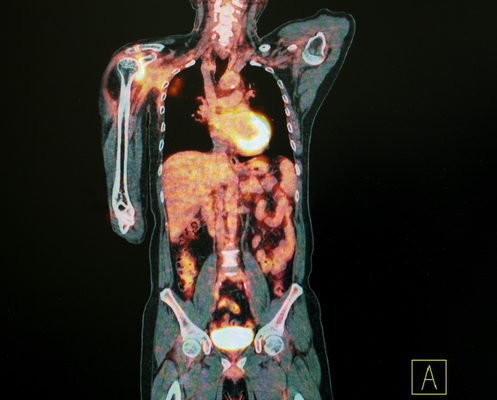

This post was originally published on this site Regeneron‘s bispecific antibody REGN1979 is showing outstanding clinical effectiveness in B-cell non-Hodgkin’s lymphoma patients who received prior treatments, including those who progressed after CAR T-cell therapies. The treatment completely eliminated the cancer in 71% of follicular lymphoma and 57% of diffuse large B-cell lymphoma patients participated in…